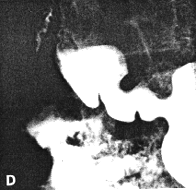

Case 29.4 F.F., 29 year old female, presented with epigastric pain and loss of weight. Radiographic examination showed an ulcer 1.5 cm in diameter on the lesser curvature of the stomach at the incisura angularis (Fig. 29.4 (A-D). A cylindrical contraction, 3.0 cm in length and containing a longitudinal mucosal fold, was seen in the pyloric region; a prominent pseudo-diverticulum was evident on the greater curvature side of the contraction, the appearances tallying with contraction of the pyloric sphincteric cylinder. Occasionally a minor degree of relaxation occurred, but most of the time the contraction remained as illustrated, with absence of normal cyclical activity. (Fig. 29.4 A-D). Response to anti-ulcer therapy was poor. Endoscopic biopsy 6 months later showed an ulcer at the angulus with surrounding induration. Microscopically the base of the ulcer consisted of fibrinopurulent material, fibrotic tissue and well-differentiated adenocarcinoma cells. Billroth II partial gastrectomy confirmed the large ulcer with indurated edges on the lesser curvature. Microscopically a well- differentiated adenocarcinoma, infiltrating locally through the muscularis externa into the subserosal tissue, was seen. The adjacent gastric mucosa showed areas of intestinal metaplasia. Microscopic examination of l7 lymph nodes revealed no carcinoma cells. It was concluded that the appearance of a chronic ulcer with dense fibro-collagenous tissue and carcinoma cells in the base, was compatible with so-called "ulcer cancer", i.e. carcinoma originating in a chronic gastric ulcer.

| Fig. 29.4 A-D Case F.F. Malignant ulcer at incisura angularis (open arrow). Constant contraction of pyloric sphincteric cylinder with absent cyclical activity (filled arrows) | |